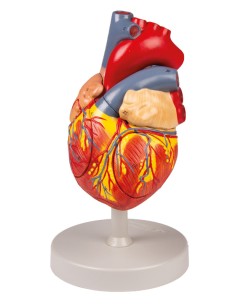

Dal cranio in 22 parti con incastri magnetici ai modelli di colonna vertebrale, da quelli di articolazioni a quelli di cuore, ogni pezzo della nostra collezione è progettato per un’immersione totale nello studio dell’anatomia umana. I nostri modelli, realizzati tramite scansioni di ossa vere, garantiscono un’esperienza tattile autentica e una fedeltà di peso quasi identica agli originali.

Essenziali per studenti e professionisti, i nostri modelli anatomici sono strumenti didattici che permettono di osservare le strutture anatomiche con precisione, eliminando la necessità di dissezioni o studi invasivi. Sono inoltre utili per spiegare ai pazienti le patologie, rendendo la comunicazione più efficace e risparmiando tempo prezioso.